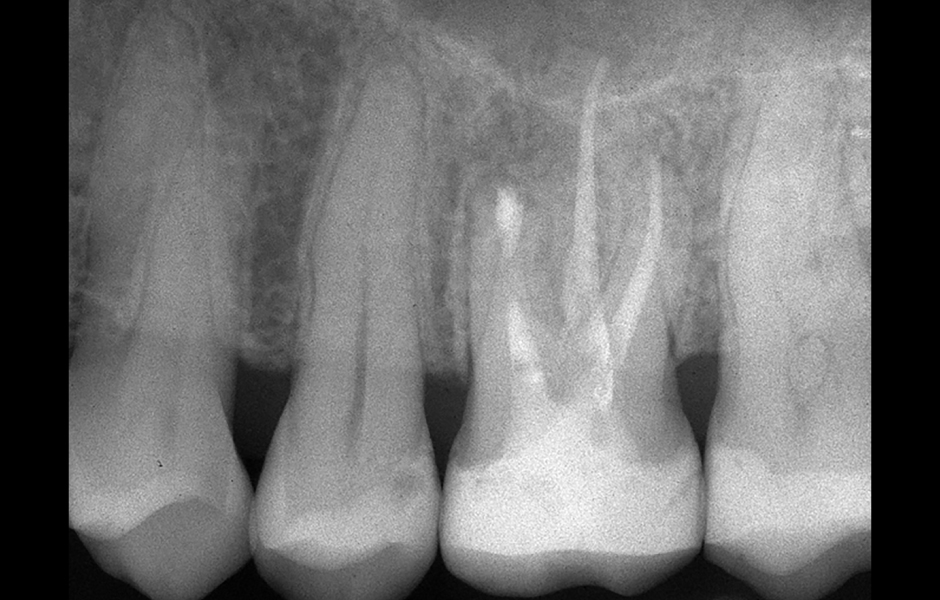

Obr. 2.8: Pooperační rentgenový snímek zobrazující obě retrográdní výplně.

Obr. 2.9: Kontrola po třech letech s kompletním zhojením obou lézí.

Obr. 4.1: Předoperační snímek horního levého prvního moláru. Oba kanálky mesiobukálního kořene byly kompletně kalcifikované a nebylo možné je ortográdně zprůchodnit.